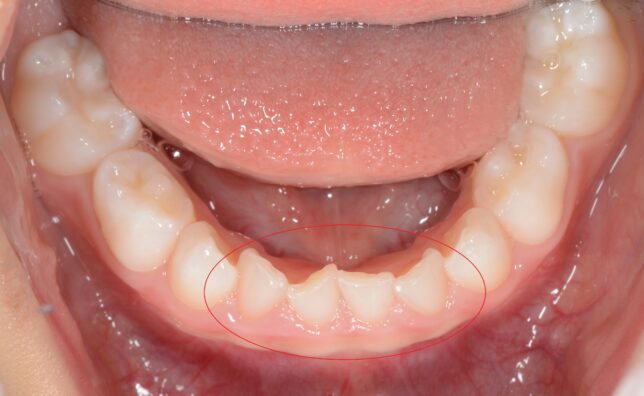

子どもが歯並びが悪いまま大人になってしまうと様々な弊害が出ます。

虫歯や歯周病、顎関節症になりやすくなる可能性があります。

歯並びが良くても上記になる可能性があるのですが、

子どものうちに歯並びや咬み合わせを治しておくだけで、随分とそのリスクが減ります。

当院がおこなっている子どもの矯正治療↓